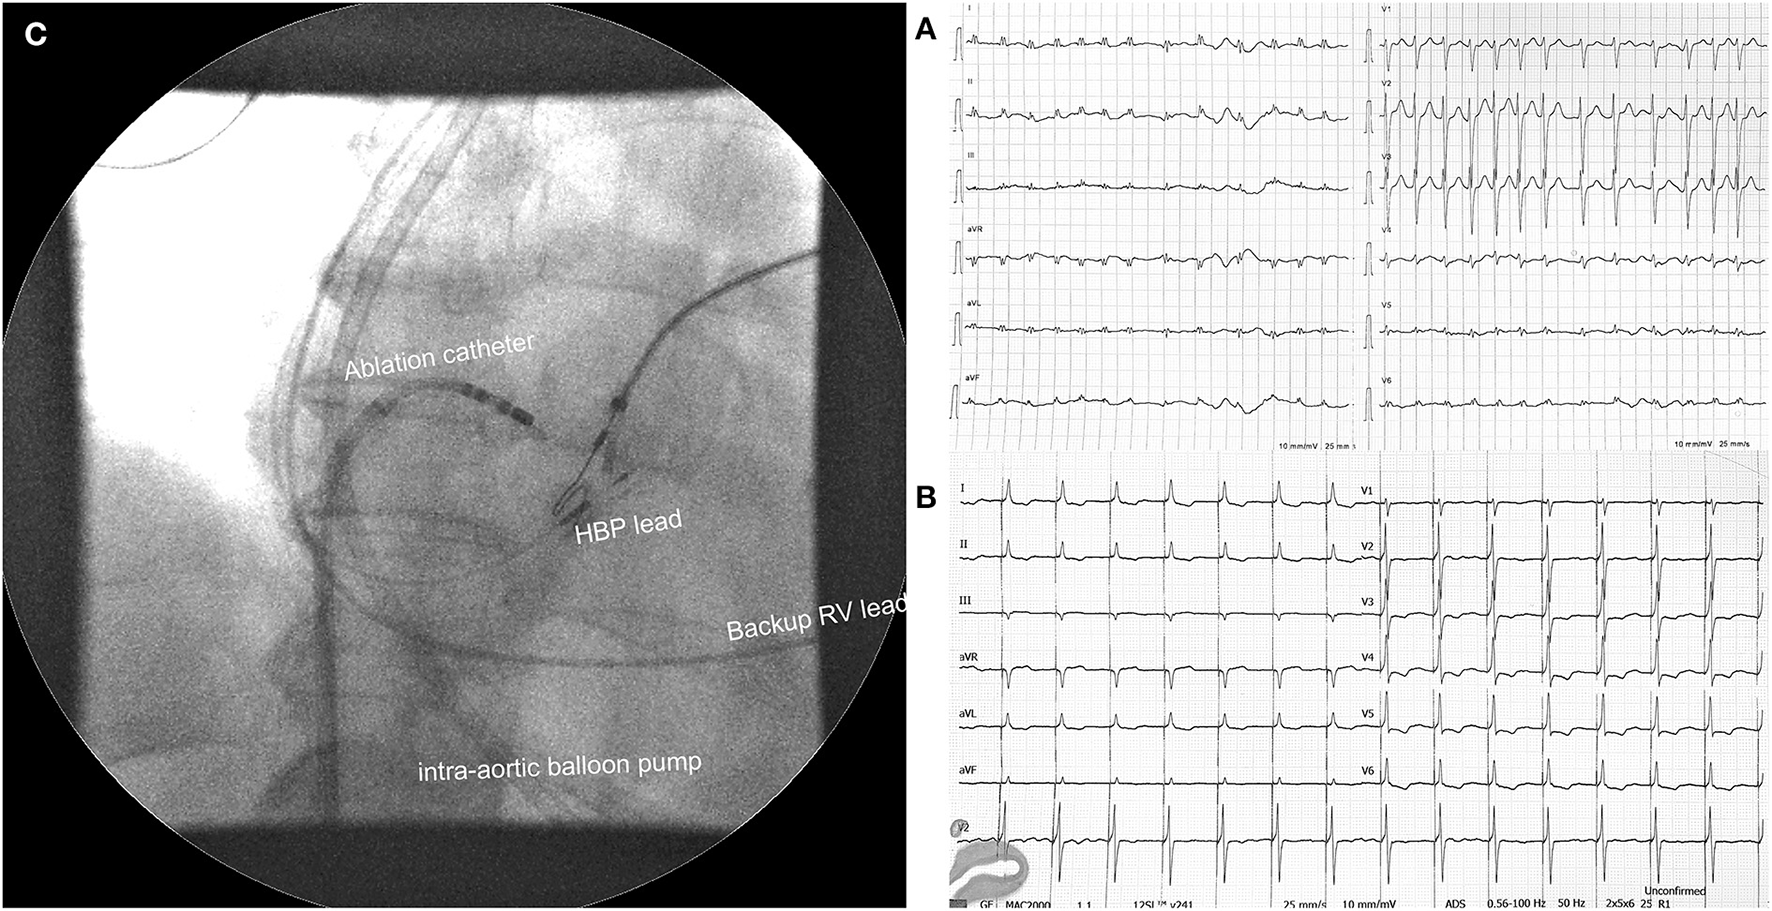

A 65-year-old woman with a history of AF, diabetes type II, and ischemic CMP was admitted due to progressive dyspnea and peripheral oedema. As she was not attending regular outpatient clinic follow-ups, the level of heart rate control or the duration of AF was not well-established. On examination at the emergency department, she was hypotensive (93/56 mmHg) with signs of cardiogenic shock. A 12-lead ECG revealed AF with a ventricular rate of around 150 bpm (Figure 1). Bedsides, echocardiography showed severely dilated LV with severely reduced EF and dilated right ventricle (RV) with reduced systolic function. The left atrium was severely dilated (Table 1). Laboratory findings showed metabolic acidosis (pH 7.32), increased lactate levels (11,4 mmol/L), acute kidney injury [creatinine levels of 164 μmol/l, glomerular filtration rate (GFR) 28 mL/min/1,73m2], severely elevated transaminases with international normalized ratio (INR) of 7, negative troponin, elevated NT-proBNP (7,024 pg/mL), and normal inflammatory markers. Initial supportive intravenous therapy did not result in clinical improvement. Invasive mechanical ventilation (MV) was initiated together with inhaled nitric oxide due to concomitant RV failure. Landiolol infusion resulted in a moderate heart rate decline from 170 to 140 bpm but shock persisted. Coronary angiography did not reveal obstructive coronary lesions. Intra-aortic balloon pump (IABP) was inserted but resulted in low augmented pressure due to tachycardia. Laboratory tests showed normal thyroid function. Bilateral stellate ganglion blockade did not result in a significant heart rate decrease. After 1 week of hospitalization and several unsuccessful synchronized EC, the “ablate and pace” strategy was attempted. Non-selective HBP was achieved with a stable pacing threshold of 2.25 V at 1 ms (Figure 1). There were no procedure-related complications. Hours after the procedure there was a significant improvement in LV function. Twenty-four h after the procedure her condition improved and IABP could be removed. We started with low dose HF therapy. Her condition further improved, and she was weaned from MV on day 17. Her blood pressure normalized, and LV function further improved. She was discharged from the hospital on day 43. At 1-year follow-up, her condition was stable (Table 1).

Figure 1

(A) Electrocardiogram at admission with visible atrial fibrillation with a ventricular rate of 150 bpm. (B) Electrocardiogram after atrioventricular node ablation and His bundle pacing. (C) Position of pacing leads and ablation catheter during fluoroscopy with visible intra-aortic balloon pump in the background. HBP, His bundle pacing; RV, right ventricle.